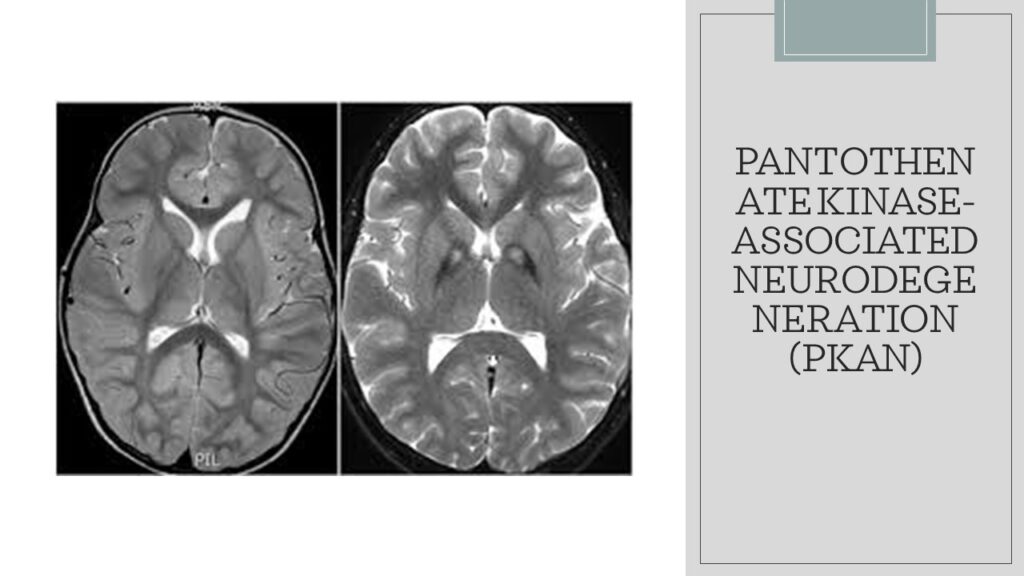

Severe Deficiency, Pantothenate Kinase-associated Neurodegeneration (PKAN) Symptoms

Severe deficiency of pantothenic acid, also known as vitamin B5, is rare in healthy individuals due to its wide availability in various food sources. However, there is a rare neurodegenerative disorder called Pantothenate Kinase-associated Neurodegeneration (PKAN) that is associated with mutations in the PANK2 gene, which plays a role in pantothenic acid metabolism. PKAN leads to a deficiency of coenzyme A (CoA), which is derived from pantothenic acid. Here are some symptoms associated with PKAN:

• Movement Disorders: PKAN is characterized by movement disorders that typically appear in childhood. These may include dystonia, which is the involuntary and sustained muscle contractions causing abnormal postures or repetitive movements. Other movement abnormalities like parkinsonism (tremors, rigidity, and bradykinesia), chorea (involuntary, jerky movements), and spasticity (increased muscle tone) may also occur

• Cognitive Impairment: PKAN can lead to cognitive impairment, including intellectual disability, learning difficulties, and impaired executive functions. Individuals with PKAN may experience difficulties with memory, attention, problem-solving, and decision-making

• Behavioural and Psychiatric Symptoms: PKAN can be associated with behavioural changes and psychiatric symptoms. These may include emotional instability, aggression, impulsivity, anxiety, depression, and psychotic features

• Eye Abnormalities: Some individuals with PKAN may develop eye abnormalities, such as optic atrophy (damage to the optic nerve) and retinal degeneration. These can lead to visual impairment and vision loss

• Speech and Language Problems: PKAN can affect speech and language development. Individuals may have speech difficulties, including dysarthria (difficulty articulating words), slurred speech, or dysphonia (hoarse or weak voice). Language difficulties, such as expressive and receptive language delays, may also be present

• Dementia: In the later stages of PKAN, individuals may experience progressive cognitive decline, leading to dementia. This includes severe memory loss, confusion, disorientation, and impaired thinking and judgment

• It’s important to note that PKAN is a progressive disorder, and symptoms can vary in severity among individuals